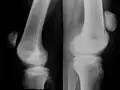

Röntgen

Mit einfachen Röntgenbildern des Kniegelenks in zwei Ebenen (von vorne und von seitlich) kann zuverlässig jeder Kniescheibenbruch diagnostiziert werden. Es zeigen sich die Bruchstücke auseinandergezogen und meist mit einem einfachen Quer- oder Schrägbruch, der der typischen Krafteinwirkung von vorne und dem einwirkenden Muskelzug entspricht. Damit liegt auch die Zerreißung der knorpeligen Gelenkfläche der Kniescheibe zur Oberschenkelrolle („patellares Gleitlager“) vor.

Bei höherer Krafteinwirkung wie z. B. bei Verkehrsunfällen oder bei schlechter Knochenstruktur (Osteoporose) kommt es zu so genannten Mehrfragmentbrüchen oder Sternbrüchen, die eine wesentlich größere Zerstörung von Knochen und Gelenkfläche bedeuten, im Prinzip aber primär die gleiche Auswirkung auf die Kniefunktion haben.

Im Röntgenbild ist die Darstellung der Mehrfragmentfraktur unsicherer, trotzdem ist hier weitere bildgebende Diagnostik mit CT oder Kernspin für einen Chirurgen nicht immer sinnvoll: Während der auf jeden Fall notwendigen Operation kann man offen alle einzelnen Fragmente identifizieren und entsprechend versorgen.